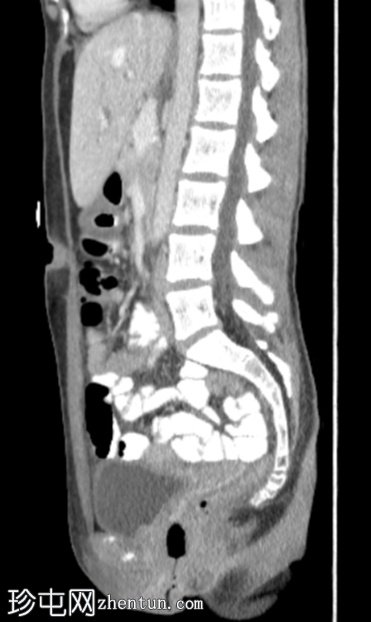

矢状位增强扫描(门静脉期)

4.png

定位片、轴位、矢状位及冠状位图像均可见阴道内有一根线状充气棉塞。棉塞的线头在本例中清晰可见。

阴道内有一根棉塞(女性卫生用品),是月经期女性在X线检查中常见的偶然发现。它们由棉和人造丝制成,容易滞留空气,因此在影像检查中,它们会呈现出阴道的形状和方向。有时,也能看到卫生棉条的线,就像本例中一样。放射科医生应该能够识别阴道卫生棉条,以免将其与病变混淆。